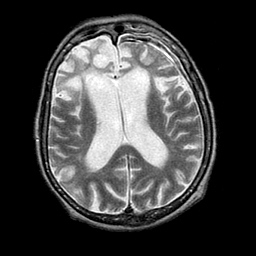

Pick's Disease, MR Study mr-t2 -- Slice #13

[Home][Help][Clinical] Slice 13